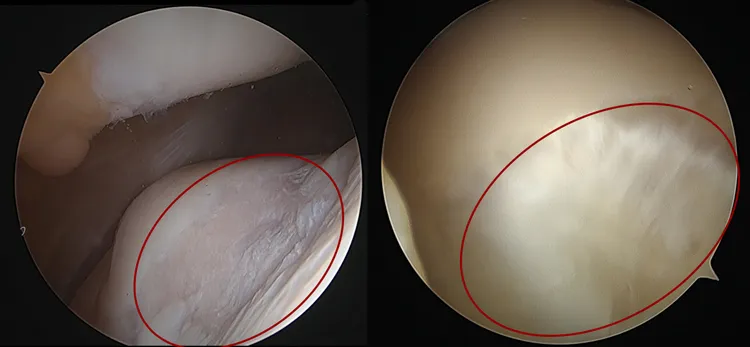

關節鏡頭下膝蓋軟骨損傷情形(左),經自體軟骨移植,成功再生(右)。中港澄清提供

女老師決定先接受右膝蓋「自體軟骨移植再生術」,王稚暉醫師指出,這項手術,是先在患者自己未受破損部位取下健康膝蓋軟骨,一個單位約2公克,共取出三個單位,再以特殊器材和技術在已破損的患部鑽三個凹槽,每個凹槽約口0.8公分,將三個單位的健康軟骨一一的種進凹槽,術後一年影像證實,原先膝蓋軟骨破損處已長出健康的軟骨組織,證實了自體軟骨再生技術的成功。